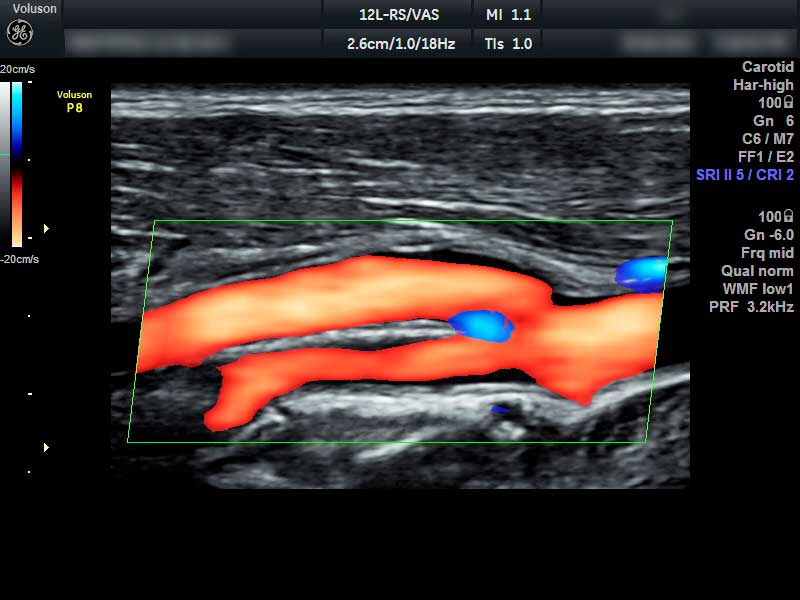

УЗИ сосудов шеи

Атеросклероз сосудов шеи – образование атеросклеротических бляшек и сужение просвета сосуда. На ранних стадиях пациент может не подозревать о патологии. Бляшки опасны стенозом, хронической ишемией мозга и возможным инсультом.

Анатомические аномалии – врожденные или приобретенные извитости, петлеобразования, аневризмы, мальформации сосудов.